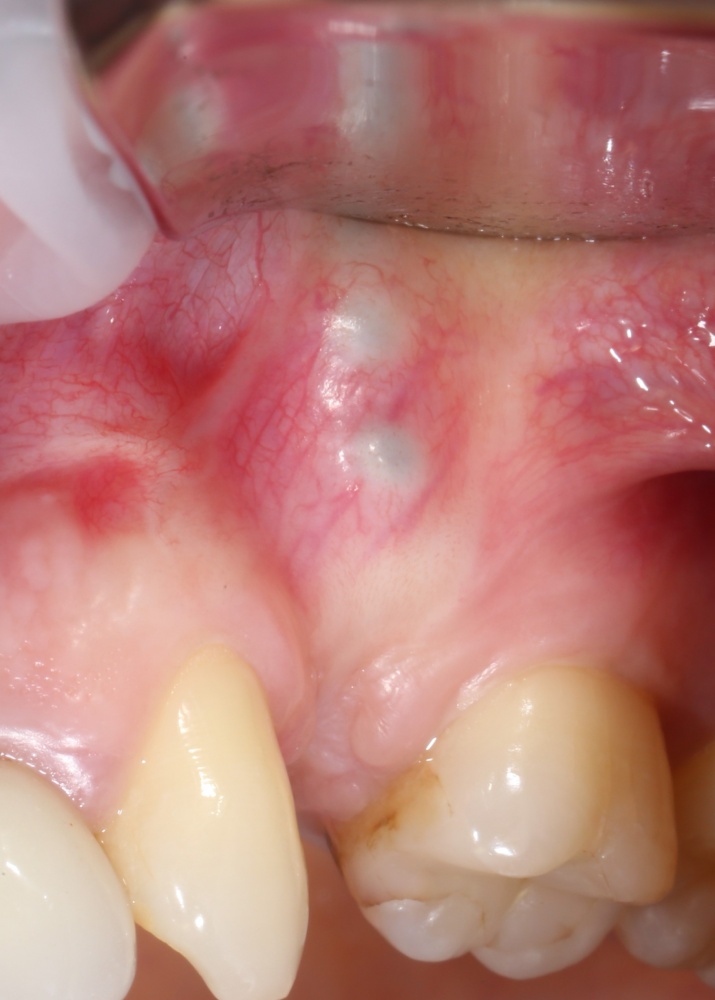

Посмотрим на результат:

особенно на то, что внутри:

Обратите внимание, что между пересаженным костным блоком и принимающим ложем нет чёткой границы, а сам регенерат по цвету и структура, практически, не отличается от альвеолярного гребня. Это как раз то, что я называю хорошим результатом остеопластической операции. Нам останется только сформировать десну и установить коронки на интегрированные имплантаты.